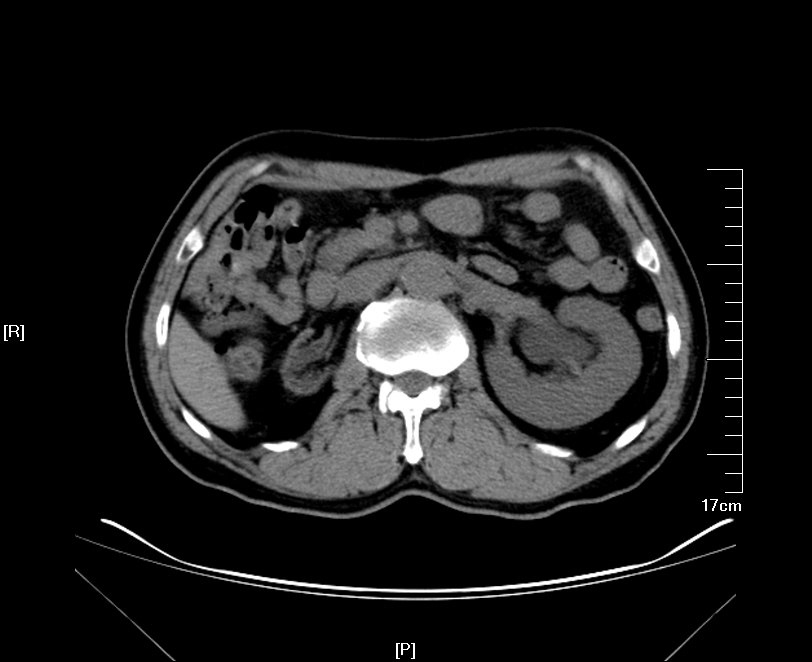

2016年02月手术患者,男性,47岁,河北人,农民,主诉双侧腰部酸胀一年余,伴尿少三天;五年前曾因输尿管结石在当地予以震波碎石3次,后疼痛缓解后未重视,五年来未予以复查,三天前出现尿少,腰部酸胀加重与当地医院就诊后发现病情危重遂来我院求诊,CT:双侧肾脏重度积水,皮质菲薄,双侧输尿管上段扩张明显,双侧输尿管中段结石,左侧结石约1.7cm,右侧约2.8cm左右,GFR:左侧11.7ml/min,右侧16.1ml/min。肾功能:Cr 516umol/L;术前诊断:双侧输尿管结石 双肾重度积水 肾功能失代偿;行双侧经皮肾穿刺造瘘术,保护肾功能,十天后Cr下降至236umol/L,方行双侧输尿管镜检,但由于输尿管梗阻时间太长,输尿管迂曲扩张明显,中段输尿管与周围脏器严重黏连,输尿管镜无法顺利上行,遂行双侧输尿管切开取石术+双侧输尿管裁剪成型术。

CT检查提示:双侧肾脏重度积水双侧输尿管中段结石 双侧输尿管上段积水扩张